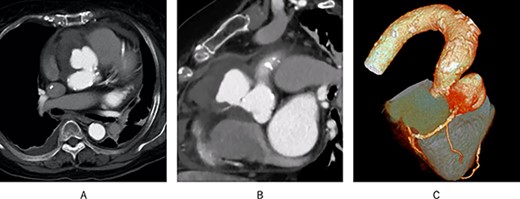

We considered performing the Bentall-De Bono operation; however, due to preoperative circulatory deterioration, we decided to perform hemi-root replacement while preserving the left sinus of Valsalva and the ostium of the LCA, resection of the right and non-coronary sinus of Valsalva, translocation of the RCA with vein graft and aortic valve replacement (AVR), as shown in Fig. 2 and Supplementary Video 1.

Post-operative schema and 3D CT; (A) the aortic root was resected diagonally, and AVR was performed; next, the vascular graft was anastomosed to the aortic root; finally, the right coronary artery was translocated using an SVG; (B) post-operative 3D CT showed that the pseudoaneurysm disappeared, and all grafts were patent.

First, the aortic root was diagonally resected with sufficient debridement of the infected tissues. Thereafter, AVR was performed, and a 26-mm J graft 1 branched (Japan Lifeline Inc, Tokyo, Japan) was anastomosed to the aortic root. Finally, the RCA was translocated using an SVG.